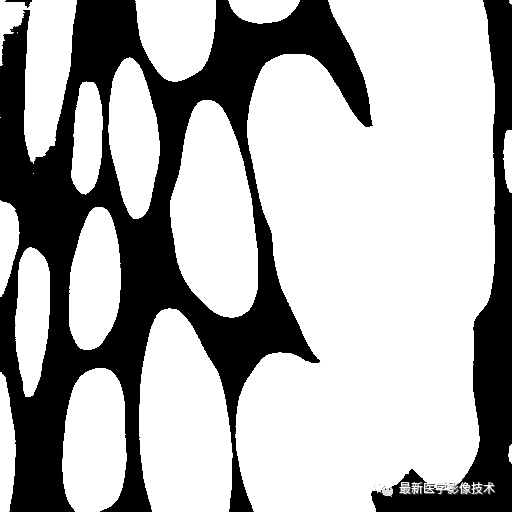

测试的原始细胞分割图像A

模型的分割图像A

测试的原始细胞分割图像B

模型的分割图像B